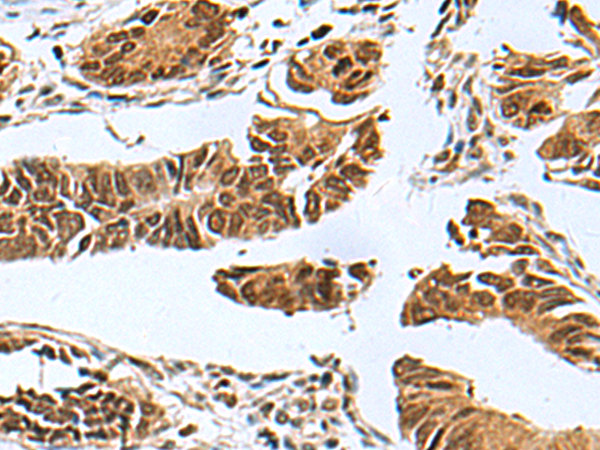

分类: 科研抗体货号: P07530别名: TFAR19应用: IHC反应种属: Human, Mouse